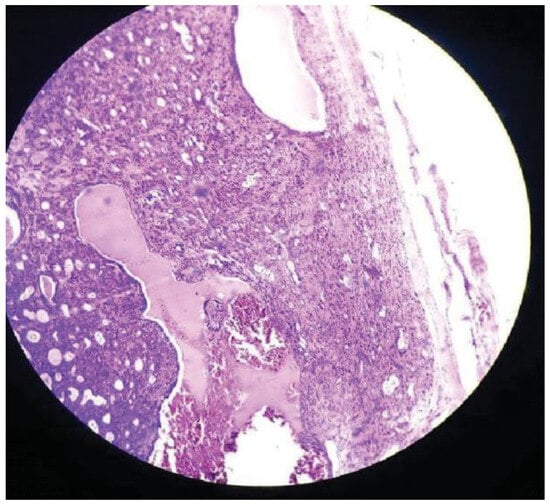

Basal Cell Adenoma of Retromolar Region from Minor Salivary Gland Origin in a 45-Year-Old Female: A Case Report

:Case Presentation